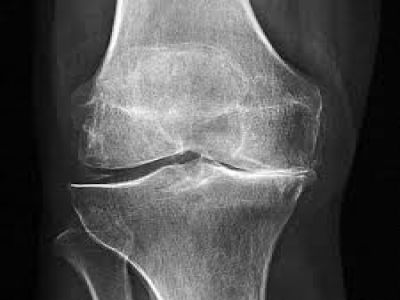

Ayakta çekilen omurganın röntgen grafisinde; bel omurgasında dejeneratif değişiklikler ve skolyoz görüldü. MR incelemesinde ise; bel bölgesindeki omurgada bir kaç seviyede bel fıtığı bulunduğu ve kanalın daraldığı belirlendi. Her iki bacağa giden sinirlerin köklerine ise bası vardı.

SF, 67 yaşında, lomber dar kanal ve dejeneratif skolyoz. Ameliyat öncesi ve sonrası radyolojik görüntüleri.